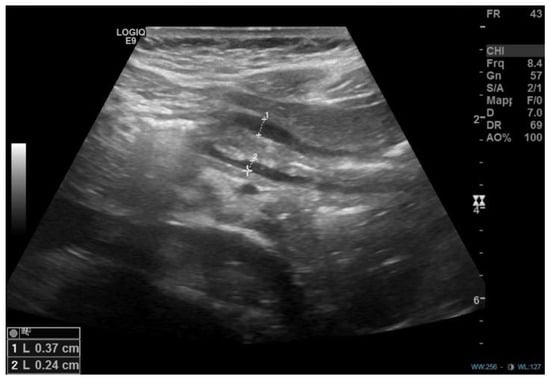

Abstract

1. Introduction

2. Discussion